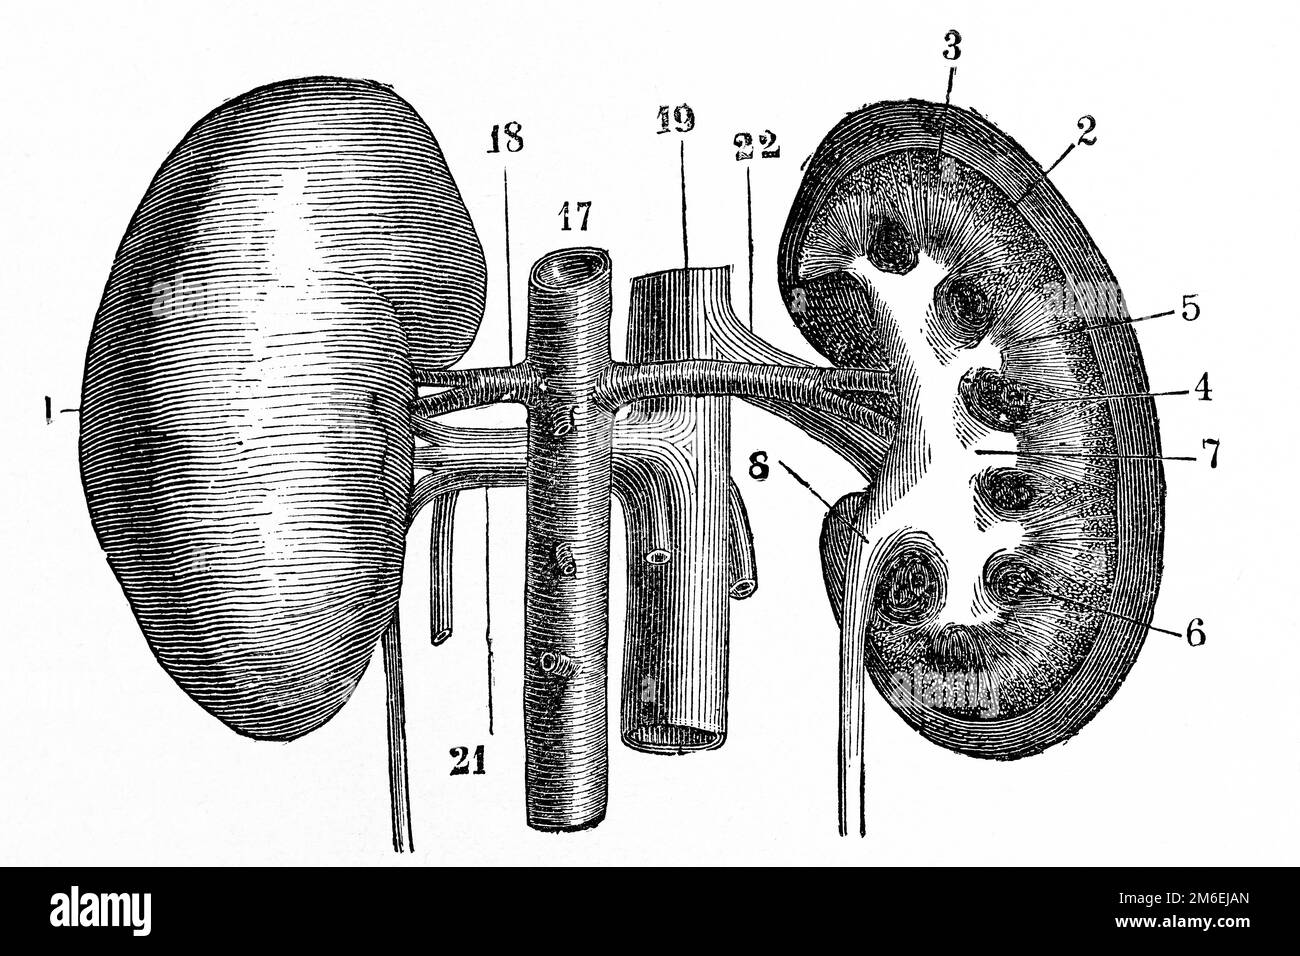

Anatomie des reins. Illustration ancienne d'un livre médical. 1889. Banque D'Imageshttps://www.alamyimages.fr/image-license-details/?v=1https://www.alamyimages.fr/anatomie-des-reins-illustration-ancienne-d-un-livre-medical-1889-image503110349.html

Anatomie des reins. Illustration ancienne d'un livre médical. 1889. Banque D'Imageshttps://www.alamyimages.fr/image-license-details/?v=1https://www.alamyimages.fr/anatomie-des-reins-illustration-ancienne-d-un-livre-medical-1889-image503110349.htmlRF2M6EJAN–Anatomie des reins. Illustration ancienne d'un livre médical. 1889.